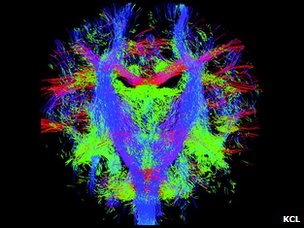

新生儿的脑神经纤维束

这张动态的脑神经路径图可以被用来“按图索骥”,解读不同的脑神经之间如何沟通、交流和联结的。

伦敦大学国王学院、帝国理工大学和牛津大学附属医院的儿科专家们的“制图”目标是希望能精确地、动态地图解脑神经信息传递线路和流程,在最细微具体的层次显示脑神经系统的发育成型过程。

这项研究的核心是MRI扫描技术的更新,使得科学家得以精确捕捉以前力所难及的胎儿脑神经系统成长的细节。